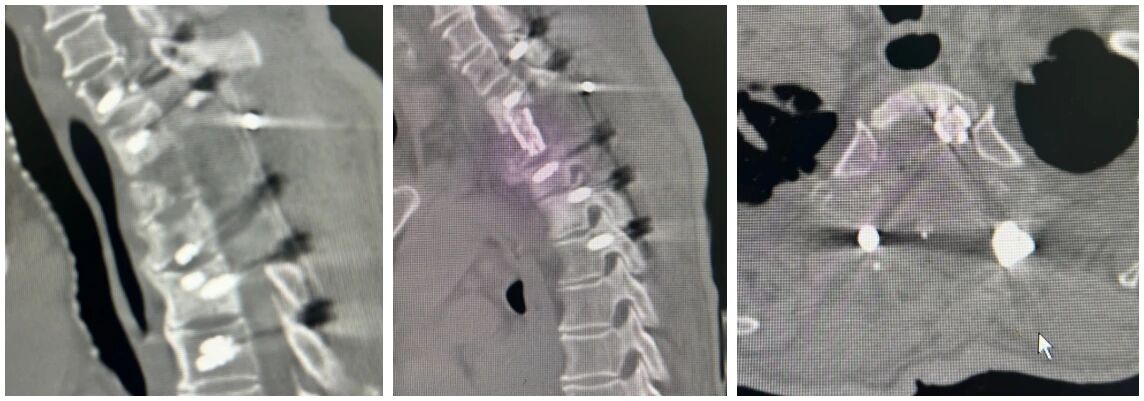

(术后摄片显示胸椎情况)

手术当日,由脊柱外科主任郭乐斌、病区副主任胡斌及主治医师陈巩舟组成的手术团队历时4小时,成功分离病灶周围组织,切除胸椎肿瘤组织,解除脊髓压迫,并进行椎体重建和内固定。

术后,在医护人员的精心照料下,彭爹恢复良好,胸背部疼痛明显缓解,未出现神经损伤等并发症,双下肢肌力逐渐恢复至3-4级,皮肤浅感觉逐步恢复,出院时可在助行器辅助下行走,这对于彭爹而言,无疑是巨大的进步与鼓舞。出院后,彭爹发来视频告知医生,已经能不需要助行器辅助自主行走。